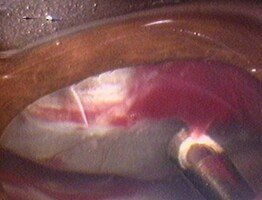

Imágenes

Vitreítis y bolas de nieve.

Banco de nieve y hemorragia vítrea.